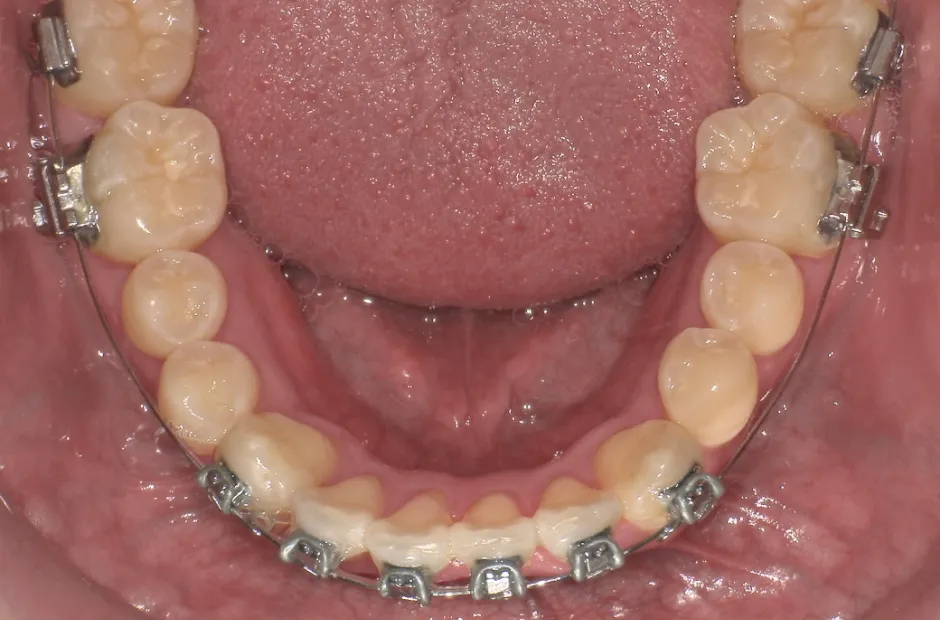

治療症例

ブラケット矯正

前歯部反対咬合

| 診断名・主訴 | 前歯部反対咬合 |

|---|---|

| 年齢・性別 | 14歳・男性 |

| 治療期間・回数 | 1年2か月 |

| 治療に用いた主な装置 | ブラケット矯正 |

| 抜歯部位 | なし |

| 治療費 | 60万円(税抜) |

| リスク・副作用 | 装置による違和感・疼痛・歯肉退縮・歯根吸収・虫歯のリスクなど |

治療前

治療中

治療後